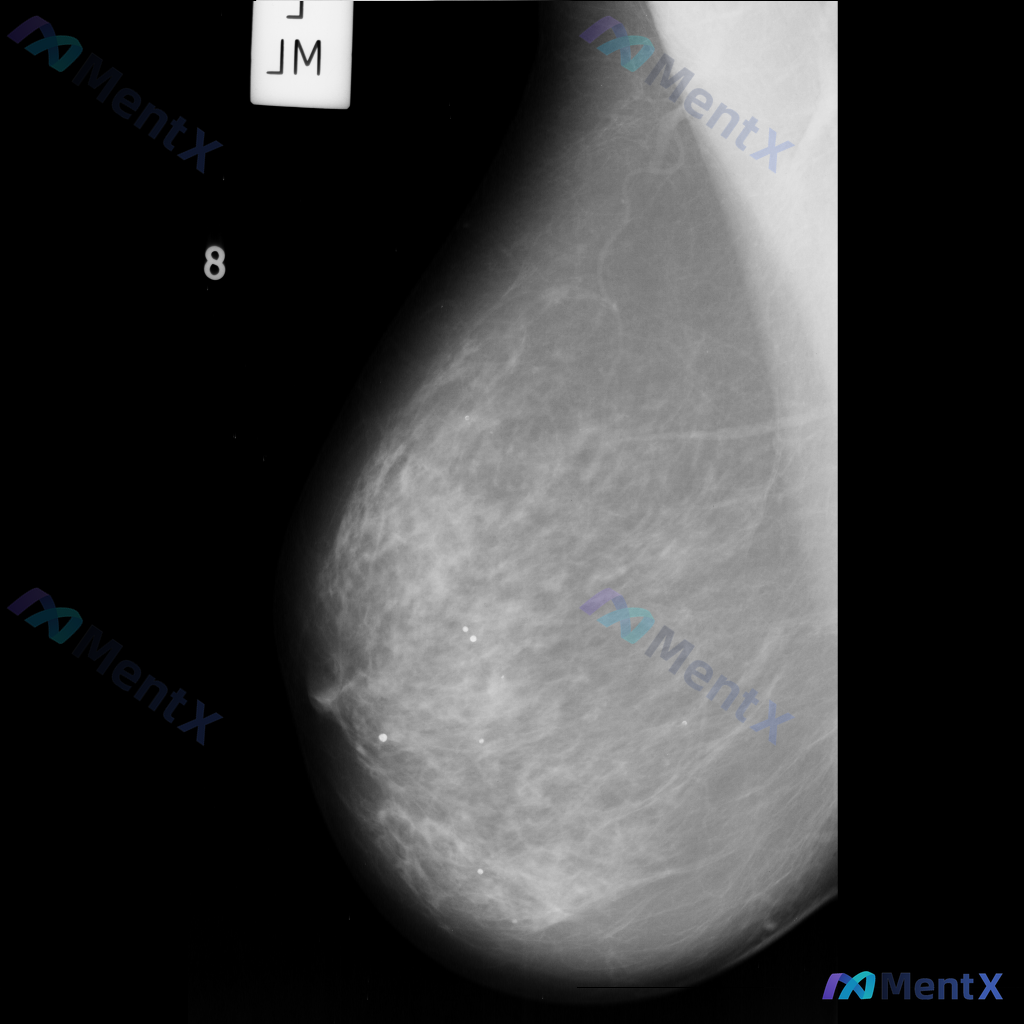

整理到一张乳腺钼靶影像资料,目前只有单张图像,没有提供双侧对比和多体位视图。 从这张图像来看,主要表现是腺体组织与脂肪组织混合存在,腺体分布相对广泛。目前没有看到非常明确的肿块、成簇钙化或明显的结构扭曲这类表现。 想跟大家讨论一下,单看目前这张影像,大家会优先考虑哪一种情况?另外,对于这类单张图像的...